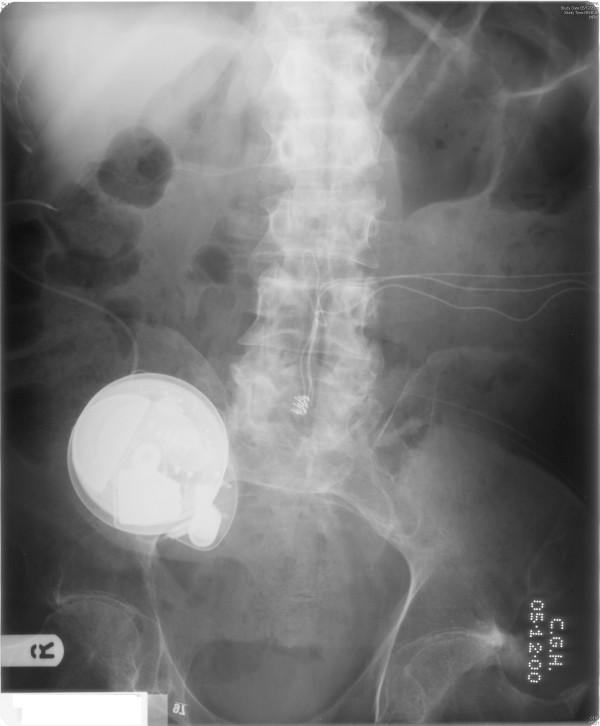

A Caucasian male, who was born in 1943, sustained paraplegia at T-4 (ASIA-B) in 1981. This patient underwent implantation of sacral anterior root stimulator in September 1985. The bladder stimulator started giving trouble since 1996 and the patient went back to using indwelling urethral catheter. In August 2006, this patient passed blood in urine after a routine change of indwelling catheter. Cystoscopy showed unhealthy bladder mucosa. Bladder biopsy revealed carcinoma, which was infiltrating bundles of muscularis propria. Many of the nests showed evidence of squamous differentiation, while others could be transitional or squamous. This patient underwent cystectomy with lymphadenectomy in March 2007 in a hospital nearer his home. Histology showed three nodes involved. This patient has been doing well since the operation.

一名1943年出生的白种男性,1981年在T-4水平(ASIA-B级)发生截瘫。该患者于1985年9月接受了骶前神经根刺激器植入术。自1996年起,膀胱刺激器开始出现问题,患者又重新使用留置导尿管。2006年8月,该患者在常规更换留置导尿管后出现血尿。膀胱镜检查显示膀胱黏膜不健康。膀胱活检显示为癌,肿瘤浸润固有肌束。许多癌巢显示有鳞状分化的证据,而其他的则可能是移行或鳞状的。2007年3月,该患者在离家较近的一家医院接受了膀胱切除术及淋巴结清扫术。组织学检查显示有三个淋巴结受累。该患者术后情况良好。